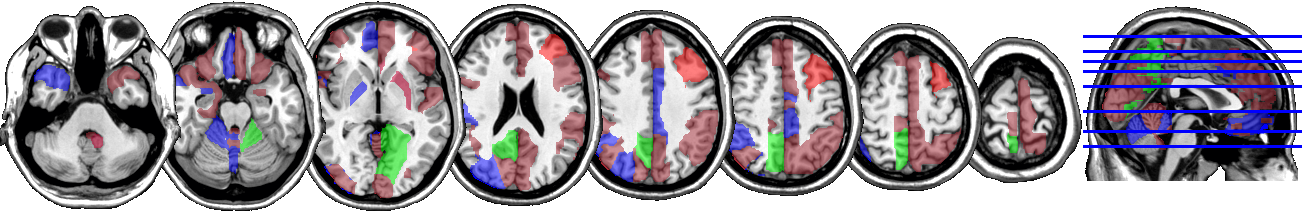

One motivating example for our methods is the application to the functional magnetic resonance imaging (fMRI). The dataset consists of the functional signals of the brain activities measured by blood-oxygen-level-dependent (BOLD), which detects hemodynamic changes based on the metabolic demands followed by neural activities. There are pre-specified regions of the brain, and the BOLD signals associated with multiple voxels in each region are integrated into one signal for that region. Thus, the fMRI data are considered to be multivariate functional data in which each functional predictor represents the signals from a region of the brain. In Section 8, we regress the ADHD index to the regional BOLD activities of the fMRI of the human subjects. There are regions of the brain in the data, and our methods reduce the regions to 41 regions with significantly lower errors than the linear functional regression. Figure 1 displays the regions of the brain’s atlas that are identified by our method. It shows that the methods simplify the data analysis and provide clear representation while keeping the crucial information. The analysis shows that there is an urgent need for new methods in the fields of medical and life sciences as well as other related areas.

In Figure 4 and Figure 5, we display the regions associated with the estimated active sets for IQ and ADHD by the MFG-LASSO respectively. The final active sets of the algorithms were extracted, and matched with the AAL’s atlas where each of the regions has a label. The regions were manually entered into the WFU picked atlas Maldjian and et al. (2003) tool of the SPM-12 ran on MATLAB 2020b to produce mask.nii files. The mask files were imported on MRIcron software to produce the multi-slice images.

The active sets cover the regions associated with IQ in Yoon and et al. (2017) such as cerebello-parietal component and the frontal component. It is mentioned in the paper that the parietal and the frontal regions are strongly associated with intelligence by maintaining a connection with the cerebellum and the temporal regions. The shaded areas cover the ones mentioned in Goriounova and Mansvelder (2019) as well. We provide the name of the regions associated with these active sets in the appendix.

It is interesting that ADHD and IQ have a large proportion of common active sets. For instance, when MFG-LASSO is applied, they overlap in ROIs where the size of active sets are and for IQ and ADHD respectively. On the other hand, the ROIs that are associated with ADHD but not with IQ are the middle and superior frontal, the Parahippocampal, the inferior parietal, and the superior temporal pole gyri. The ratio of the number of right hemisphere regions to the left ones associated with IQ is significantly greater than that of ADHD.